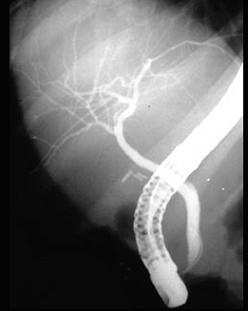

问题 下列各图为何种胆道造影方式 ( )

选项 A、内镜逆行胰胆管造影(ERCP) B、磁共振胆胰管造影(MRCP) C、静脉胆道造影 D、经皮肝穿刺胆道造影(PTC) E、口服胆囊造影

答案 A